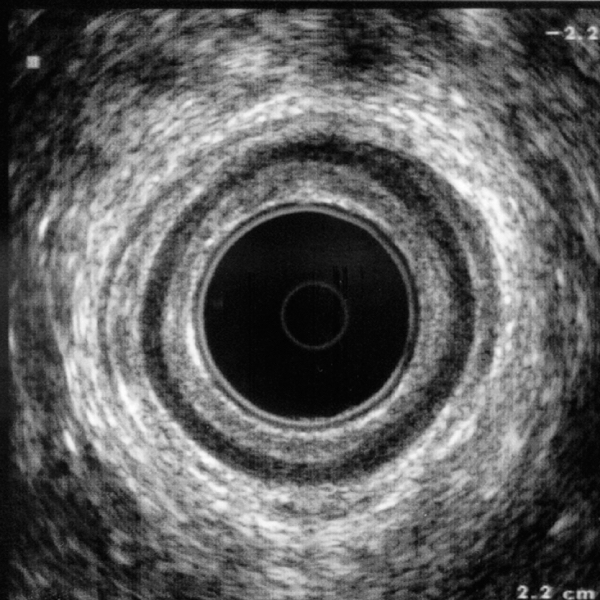

Realización de Ultrasonido Endoanal y Endorectal 360°